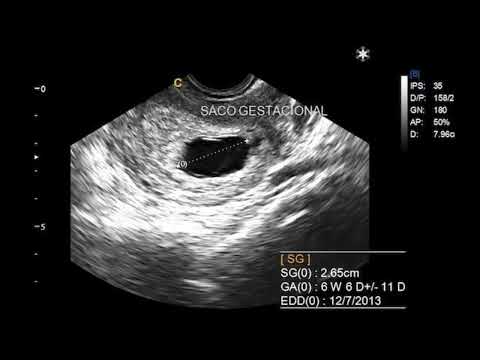

3. Medición promedio del saco gestacional a las 6 semanas

La medición promedio del saco gestacional a las 6 semanas es una información crucial para las mujeres embarazadas y sus médicos. El saco gestacional es una estructura que se forma en el útero durante las primeras etapas del embarazo y alberga al embrión en desarrollo. Conocer su tamaño y crecimiento es fundamental para monitorear el progreso del embarazo y detectar posibles complicaciones.

Según estudios y datos médicos, a las 6 semanas de gestación, el saco gestacional generalmente tiene un tamaño promedio de alrededor de 10 a 20 milímetros. Sin embargo, es importante tener en cuenta que cada embarazo es único y pueden existir variaciones en dicha medida. Por eso, la medición precisa del saco gestacional se realiza a través de ecografías transvaginales o abdominales por parte de un profesional de la salud.

La medición precisa del saco gestacional es crucial para determinar la viabilidad del embarazo. A través de la ecografía, los profesionales de la salud pueden medir el diámetro del saco gestacional y compararlo con las semanas de gestación para evaluar el desarrollo del embrión. Una medida consistente con la edad gestacional esperada es un buen indicador de un embarazo saludable.